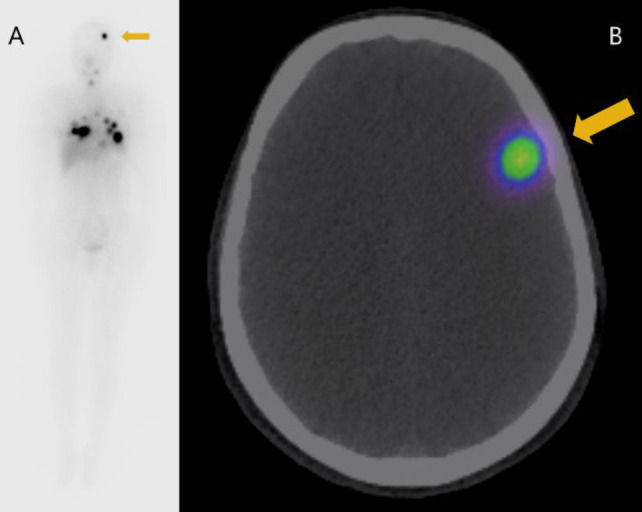

Brain metastasis (BM) occurs only in about 1% of differentiated thyroid carcinoma (DTC) cases. Although DTC generally has a good prognosis, once BM develops, the mortality rate significantly increases up to 78%. BM is usually treated by surgical resection or external radiotherapy, whereas radioactive iodine therapy (RAIT) using I-131 is much less often chosen because BM often shows poor uptake of I-131. In addition, even in case I-131 accumulates in the BM, RAIT could cause adverse effects such as brain hemorrhage and cerebral edema. We present a case of BM from DTC that showed response to I-131 therapy with no severe adverse effects. The brain lesion was very small and asymptomatic, and was only found after a post-therapy I-131 scintigraphy. There are a few case reports where BM was cured by RAIT with little to no side effects. We theorize that BM that is small in size, asymptomatic and show I-131 accumulation could be successfully treated with RAIT.